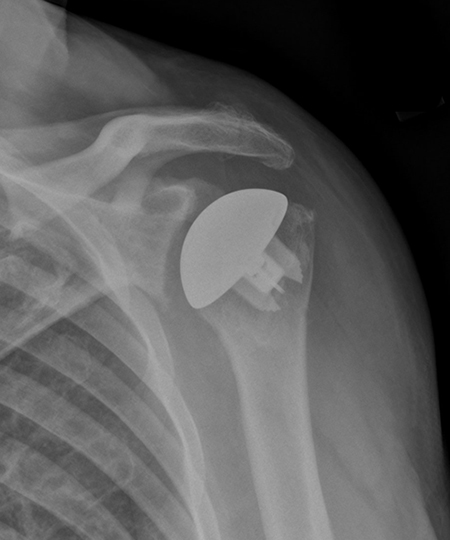

Figure 1: X-ray showing osteoarthritis of the shoulder joint, in which bones of the shoulder joint are in direct contact.

Figure 3 (left): X-ray showing a traditional total shoulder replacement. Figure 4 (right): The Comprehensive Primary Shoulder System designed by HSS surgeons.